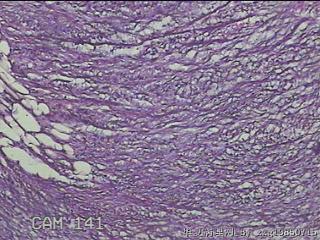

左肘部包块

性别

男

年龄

39

临床诊断

左肘部肿物:炎性脂肪瘤

一般病史

发现左肘部肿物1周。

标本名称

大体所见

灰白粉红色组织2x1.8x0.3㎝一团,表面结节状,光滑,切面灰白粉红色,质软。

图3

纤维组织细胞瘤

有外伤史吗,考虑结节性筋膜炎。

首先考虑结节性筋膜炎。

梭形细胞肿瘤,待免疫组化